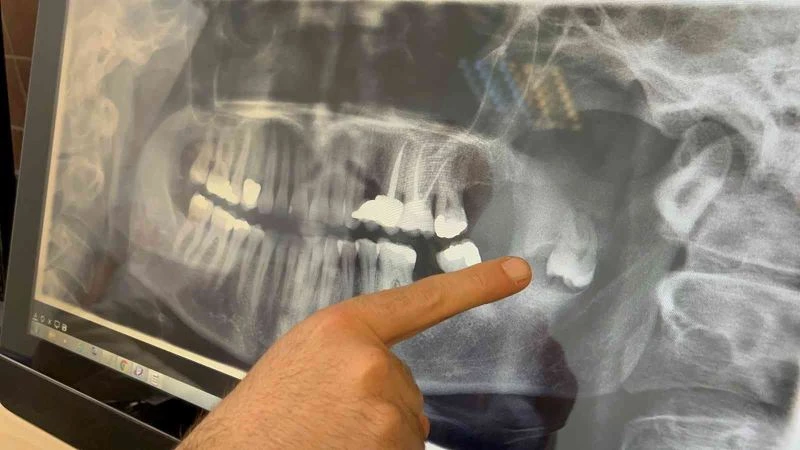

Sevan Kazak Ertural, yaklaşık 12 yıl önce bir panoramik röntgende fark ettikleri gömülü dişin çene kemiğindeki ramus bölgesinde yer aldığını söyledi. Bir zararı olmadığı ve riskli bölgede olduğu için bu dişi almaya kimsenin yanaşmadığını belirten Ertural, “Daha sonrasında dişin kistleştiğini ve çene kemiğime zarar verdiğini fark ettik. Çene kemiğimin bir kısmını eritmişti. Tekrar yaptığım başvurularımda kalıcı yüz felci olabileceğini, çenemin kırılabileceğini, sinire çok yakın olduğu için kolayca müdahale edilemeyeceğini söylediler. Bu sene içinde Ömür Hoca ile tanıştım, buraya başvurdum. Sağ olsun beni çok cesaretlendirdi, bütün riskleri anlattı. Korkmamam gerektiğini söyledi ve ondan güven alarak burada ameliyat olmaya karar verdim” dedi.

Süreç hakkında bilgi veren Doç. Dr. Ömür Dereci, hastanın yaklaşık birkaç ay önce çenesinde ciddi bir ağrı şikâyetiyle kliniğe başvurduğunu kaydetti. Doç. Dr. Dereci, “Yapılan incelemelerde çenesinde tamamen pozisyonu bozuk, ters dönmüş ve yukarı doğru çenenin derin taraflarına doğru ilerlemiş bir diş ve bu dişle ilişkili bir kiste rastladık. Cerrahi bir operasyonla hastamız tamamen uyutularak ameliyat edildi ve bu diş ve ilişkili kist buradan tamamen çıkarıldı. Yapılan muayene ve kontrollerde gayet iyi iyileştiği gözlendi” diye anlattı.